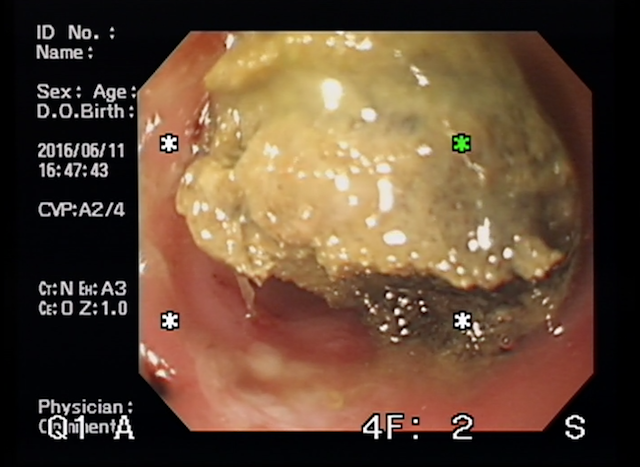

お腹のエコー検査を行うと、胃の中に液体が溜まっており、胃の出口に異物を疑うような所見がありました。

飼い主さんの同意のもと内視鏡検査を行うと、胃の出口に何やらあります。

内視鏡での除去が一番なのですが、この異物、胃の出口にガッチリはまっていまして内視鏡での除去は困難と判断し、開腹し、除去。こんなのが出てきました。

異物を確認してもらうと、スリッパのソールだということが判明。